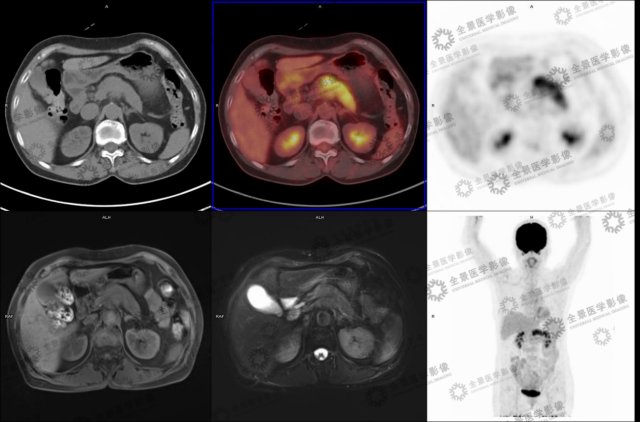

实例一

病史:女 70 岁 腹部不适,纳差半月,CT:胰腺 MT 伴小网膜囊淋巴结肿大及血管侵犯。

病灶呈延迟强化,FDG 代谢增高,考虑胰腺癌。